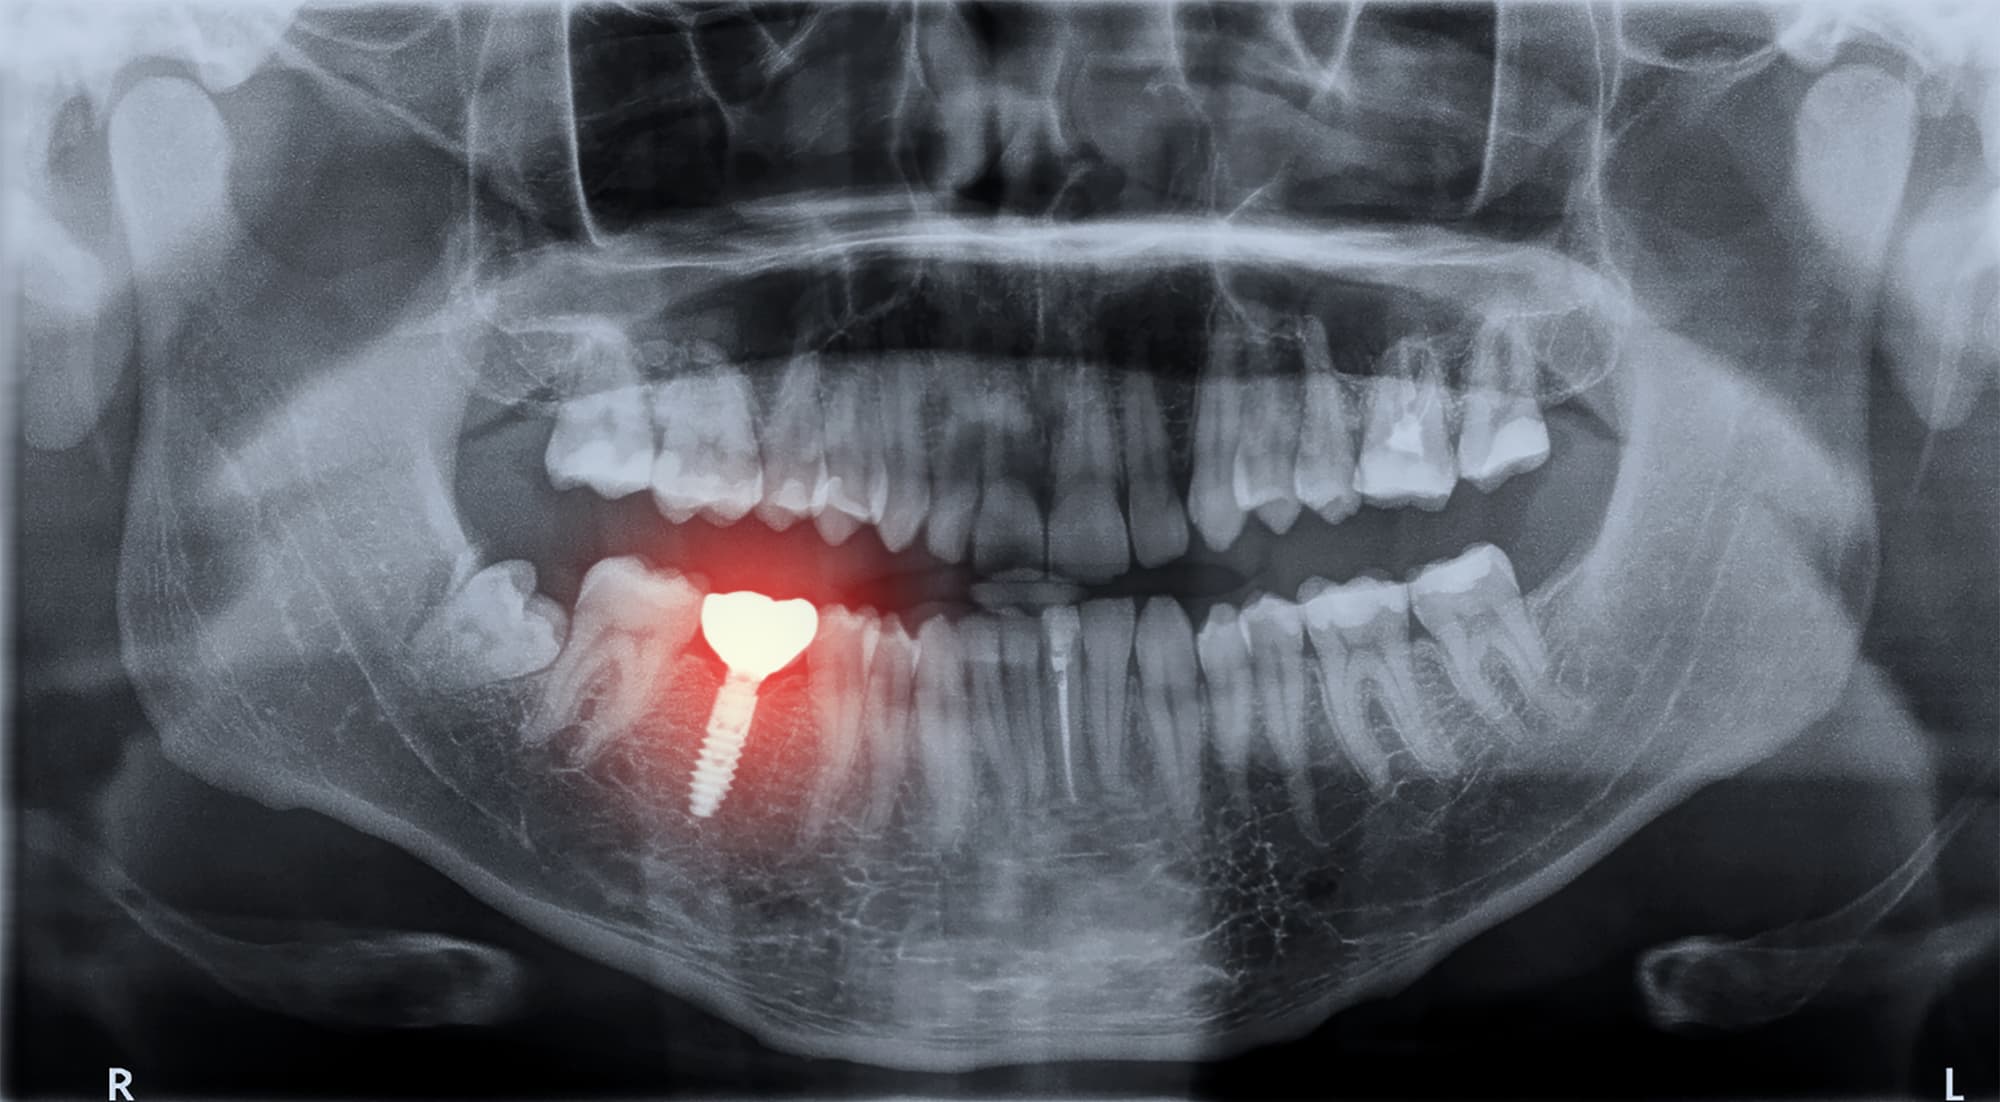

インプラントは、天然歯に近い見た目や噛み心地を再現できる治療法です。多くのメリットがある一方で、インプラント周囲炎に注意しなければなりません。

インプラント周囲炎は、インプラントの周囲の歯茎や顎の骨で炎症を起こす病気です。

インプラント周囲炎とは、インプラントの周囲に炎症が起こり、進行するとインプラントを支える顎の骨が破壊されていく病気です。天然歯に起こる歯周病に似た病気ですが、インプラントには歯根膜がなく、骨と直接結合しているため、進行の仕方や治療法に違いがあります。

炎症が歯茎の粘膜までにとどまっている段階では、インプラント周囲粘膜炎と呼ばれます。この段階では、歯茎に赤みや腫れが見られますが、痛みなどの自覚症状がほとんどありません。そのため、気づかないまま進行することも少なくありません。

進行すると、インプラントを支えている顎の骨が少しずつ破壊されていきます。土台がなくなっていくとインプラントがぐらつき、最終的に脱落することがあります。